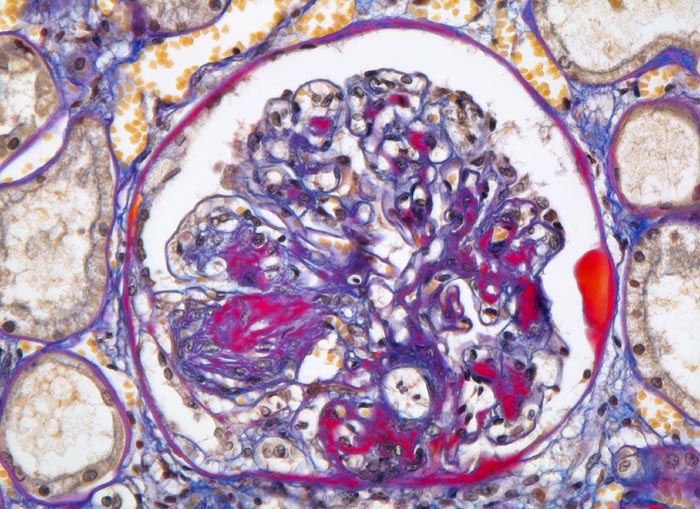

Morphologische Merkmale:

• Verbreiterung des Mesangiums mit Ausbildung von Knoten(noduläre Glomerulosklerose).

• Exsudative Läsionen: Hyaline Schlingenkappen (Proteinthromben in Glomerulumschlingen, im virtuellen Präparat nicht sichtbar) und Kapseltropfen (Proteinablagerungen im Bowman’schen Kapselraum).

• Arteriolosklerose von Vas afferens und efferens (Gefässwandhyalinose durch Ablagerung von Plasmaproteinen und Lipiden in der Gefässwand).

Im allgemeinen ist die Niere infolge von Glomerulumhypertrophie und Tubulushyperplasie vergrössert und derb, die Oberfläche ist granuliert. Bei schwerer Atherosklerose und fortgeschrittener Niereninsuffizienz kann die Niere auch normal gross oder verkleinert sein. Die Kombination von nodulärer Glomerulosklerose, hyalinen Schlingenkappen (=Proteinthromben in den Glomerulumschlingen (> 1916)) oder Kapseltropfen (> 1907) und Arteriolosklerose in Vas afferens und efferens ist beweisend für eine diabetische Nephropathie. Jede einzelne Läsion für sich genommen ist aber unspezifisch. Eine noduläre Glomerulosklerose kann auch vorkommen bei membranoproliferativer Glomerulonephritis (> 2652), Leichtkettenglomerulopathie oder Amyloidose (> 2019). Der nodulären Glomerulosklerose geht bei Diabetikern eine diffuse Glomerulosklerose (> 1906) voraus. Dabei zeigen die glomerulären Basalmembranen und das Mesangium eine progrediente gleichförmige Verbreiterung. Bei der nodulären und diffusen Glomerulosklerose handelt es sich aber wahrscheinlich um zwei pathogenetisch unterschiedliche, sich überlagernde Krankheitsbilder. Typisch bei Diabetikern ist im Unterschied zur arteriellen Hypertonie die Arteriolosklerose von Vas afferens und efferens (> 1911) und oft auch der Vasa recta. Intrarenale Arterien können eine Atherosklerose mit Atheromen zeigen. Subendotheliale Proteinablagerungen teilweise mit Verschluss der Glomerulumschlingen (Schlingenkappen) und knotige Proteinablagerungen in der Bowman'schen Kapselbasalmebran (Kapseltropfen) gehören zu den sogenannten exsudativen Läsionen (> 1919) (> 1920) der diabetischen Nephropathie und führen zu Synechien sowie zur globalen Glomerulosklerose. Gleichzeitig mit den Glomerulumveränderungen treten tubuläre Basalmembranverbreiterungen auf, später eine Tubulusatrophie und interstitielle Fibrose mit Begleitentzündung. Auch die Basalmembranen der peritubulären Kapillaren sind verdickt.